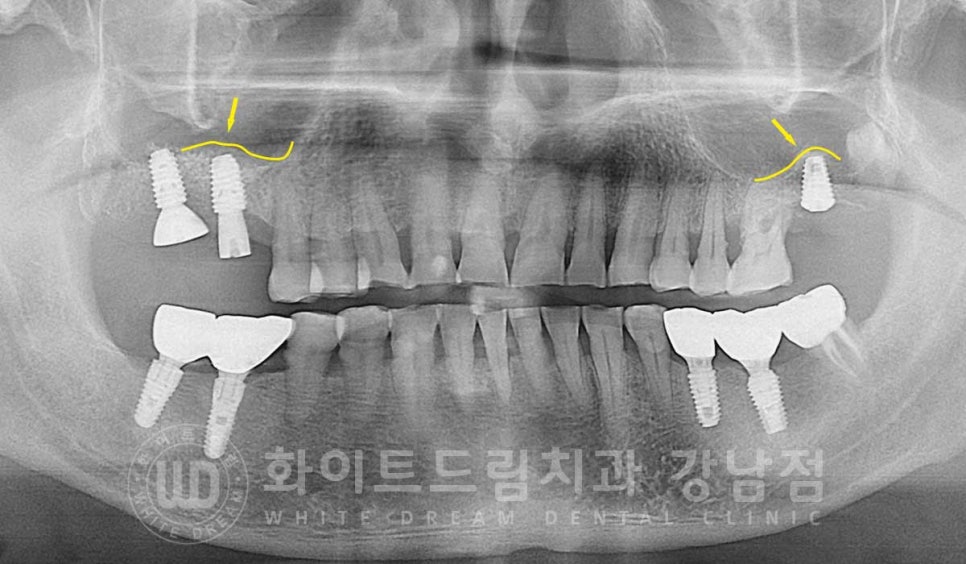

▲ 흔들리는 어금니크라운 제거 후 임플란트 즉시 식립 : 24.03.02

환자분은 잇몸 염증으로 잇몸뼈의 소실이 심했기에

뼈이식이 동반되어야 하는 상태였는데요.

게다가 상악동이 아래쪽에 위치하고 있으신 분이었기에

16, 27번 임플란트 치료는 상악동 거상술을 동반하여 수술을 진행하게 되었습니다.

상악동 거상술을 진행하면 X-RAY 상에서 임플란트 위쪽으로 둥근 돔 형태를 확인할 수 있습니다.

상악동이 예쁘게 잘 들어 올렸다는 것을 의미하고

시간이 지난 후 수술 부위가 아물고, 새로운 뼈가 잘 형성이 되면

이렇게 뼈이식 위쪽으로 하얗게 치밀골이 형성되어 있는 것이 확인된답니다.